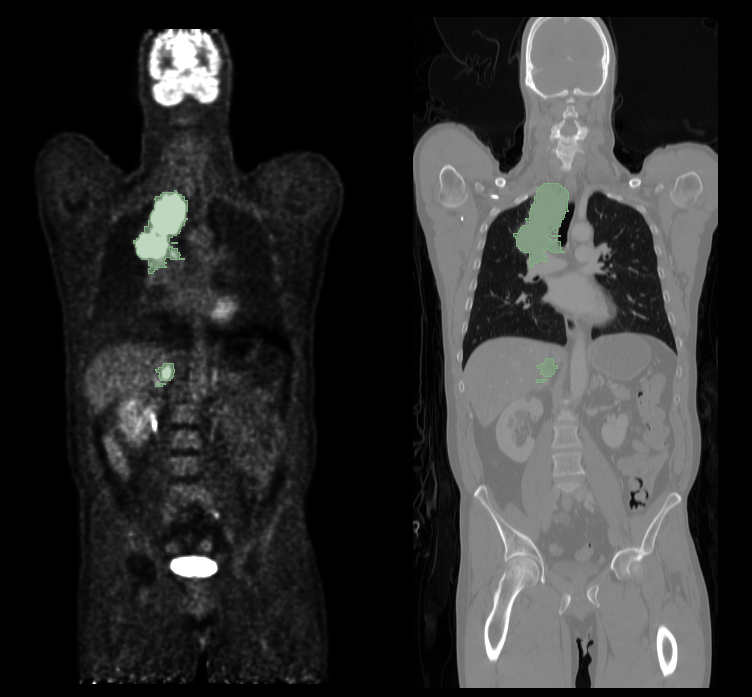

For computer-assisted cancer detection and treatment, automatic tumor segmentation from medical images is a crucial step. Deep learning has recently been effectively used for this problem, improving performance [1]. However, most deep learning segmentation techniques currently in use are limited to one imaging modality. Today’s clinics frequently use PET/CT scanners, which combine PET and CT into one device and deliver metabolic and anatomical data. The particular challenge of lesion segmentation in FDG-PET resides in the fact that healthy organs, such as the brain, bladder, etc, can have high FDG uptake, making it challenging to avoid false positive segmentations, which can be seen in Fig 1. Various studies have been proposed to segment tumors in PET/CT scans autonomously. To get constant segmentation masks between PET and CT, Song et al. created an adaptive context term for the target function [2]. In order to get object seeds, Ju et al. adopted a random walk approach as an initial preprocessing. After that, a graph cut method was applied to segment lung tumors on PET/CT images [3]. Based on the Markov Random Field optimization issue, Han et al. developed a PET/CT segmentation formulation [4]. All of the aforementioned studies showed that integrating the data from multiple imaging modalities might produce tumor segmentation results that are more precise than the segmentation results obtained from a single image modality.

We used an annotated oncologic PET/CT data set in this study. Between 2014 and 2018 at the University Hospital Tübingen, 501 consecutive whole-body FDG-PET/CT data sets of patients with malignant lymphoma, melanoma, and non-small cell lung cancer (NSCLC) and 513 data sets without PET-positive malignant lesions (negative controls) were studied [5]. Additionally, 60 minutes after receiving an I.V. injection of 300–350 MBq 18F-FDG, a full-body FDG-PET scan was performed for each patient. PET data were rebuilt using the ordered-subset expectation maximization (OSEM) technique, which had a gaussian kernel of 2 mm, 21 subsets, and two iterations on a 400 x 400 matrix. Fig. 1 shows an example of fused whole-body FDG-PET/CT data.

Refer to caption

Figure 1: An illustration of fused whole-body FDG-PET/CT data. The manually segmented malignant lesions are shown in the green sections.